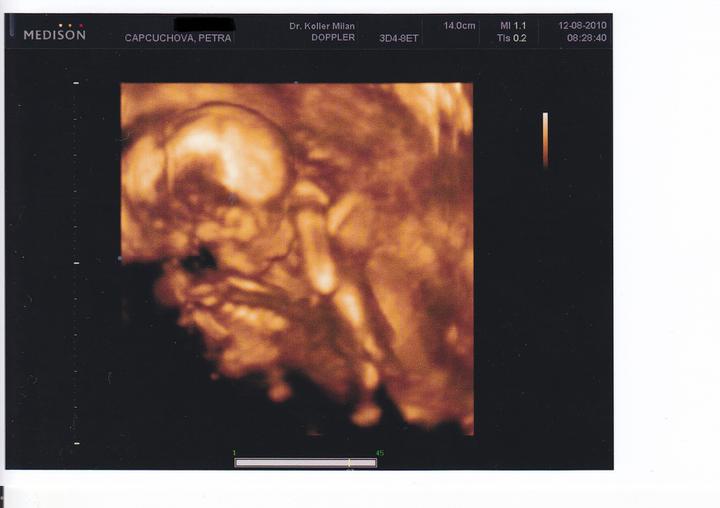

Při druhém pokusu jsme se s doktorkou dohodly, že nastoupím na dlouhý protokol, aby se mi vytvořilo víc kvalitních vajíček. Začala jsem stimulovat od půlky února a koncem dubna šla na odběr folikulů. A taky že to pomohlo, vytvořilo se víc kvalitních vajíček. V Sanatoriu jsem řekla embryologovi, jaký jsem měla posledně problém, a sama mi nabídla, že teda necháme PK na 5 dnů, aby viděli, jak se vyvýjejí a jak to zvládají. 1.5.2010 jsme si jeli do Prahy pro naše embroušky, dokonce vydrželi ještě další dva, které mi dali zamrazit do zálohy.

13.5. jsem byla na odběrech hcg, jehož hodnota byla 994, hodnota byla dost vysoka na 13. den.